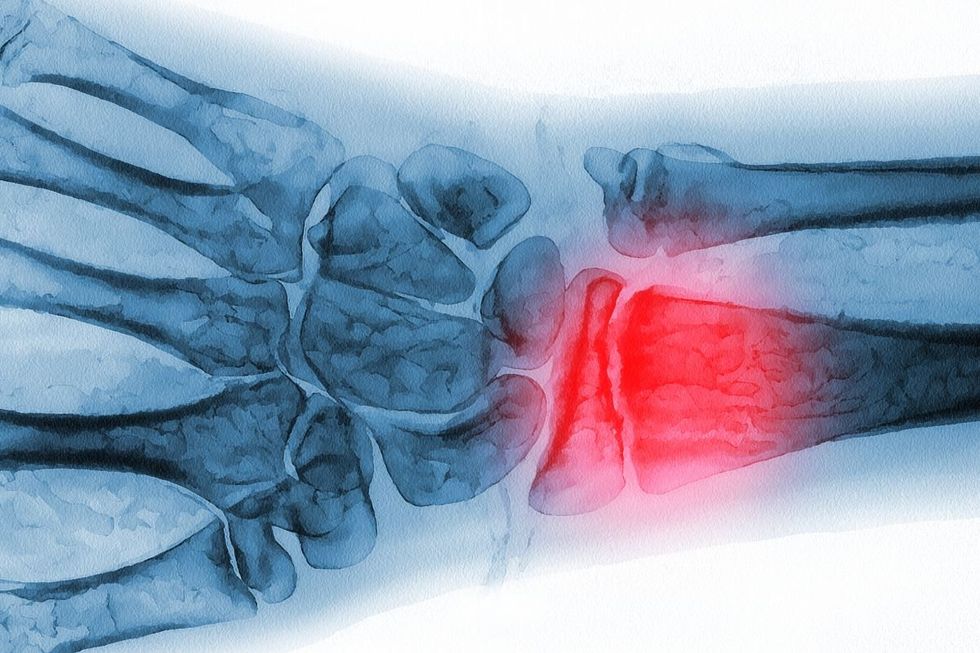

Britons are being urged to check their bone health before problems arise

A new initiative supported by the Queen is encouraging Britons to spend just three minutes checking if they're at risk of developing osteoporosis.

The online assessment was created by the Royal Osteoporosis Society to help millions get diagnosed and treated sooner.

It comes as around 3.5 million people across the UK are thought to be living with osteoporosis, yet many don't realise they could be affected until it's too late.

What's more, figures show most of us have never given our bone health a second thought, with a YouGov poll of over 2,000 adults showing that 79 per cent have never checked how their bones are doing.